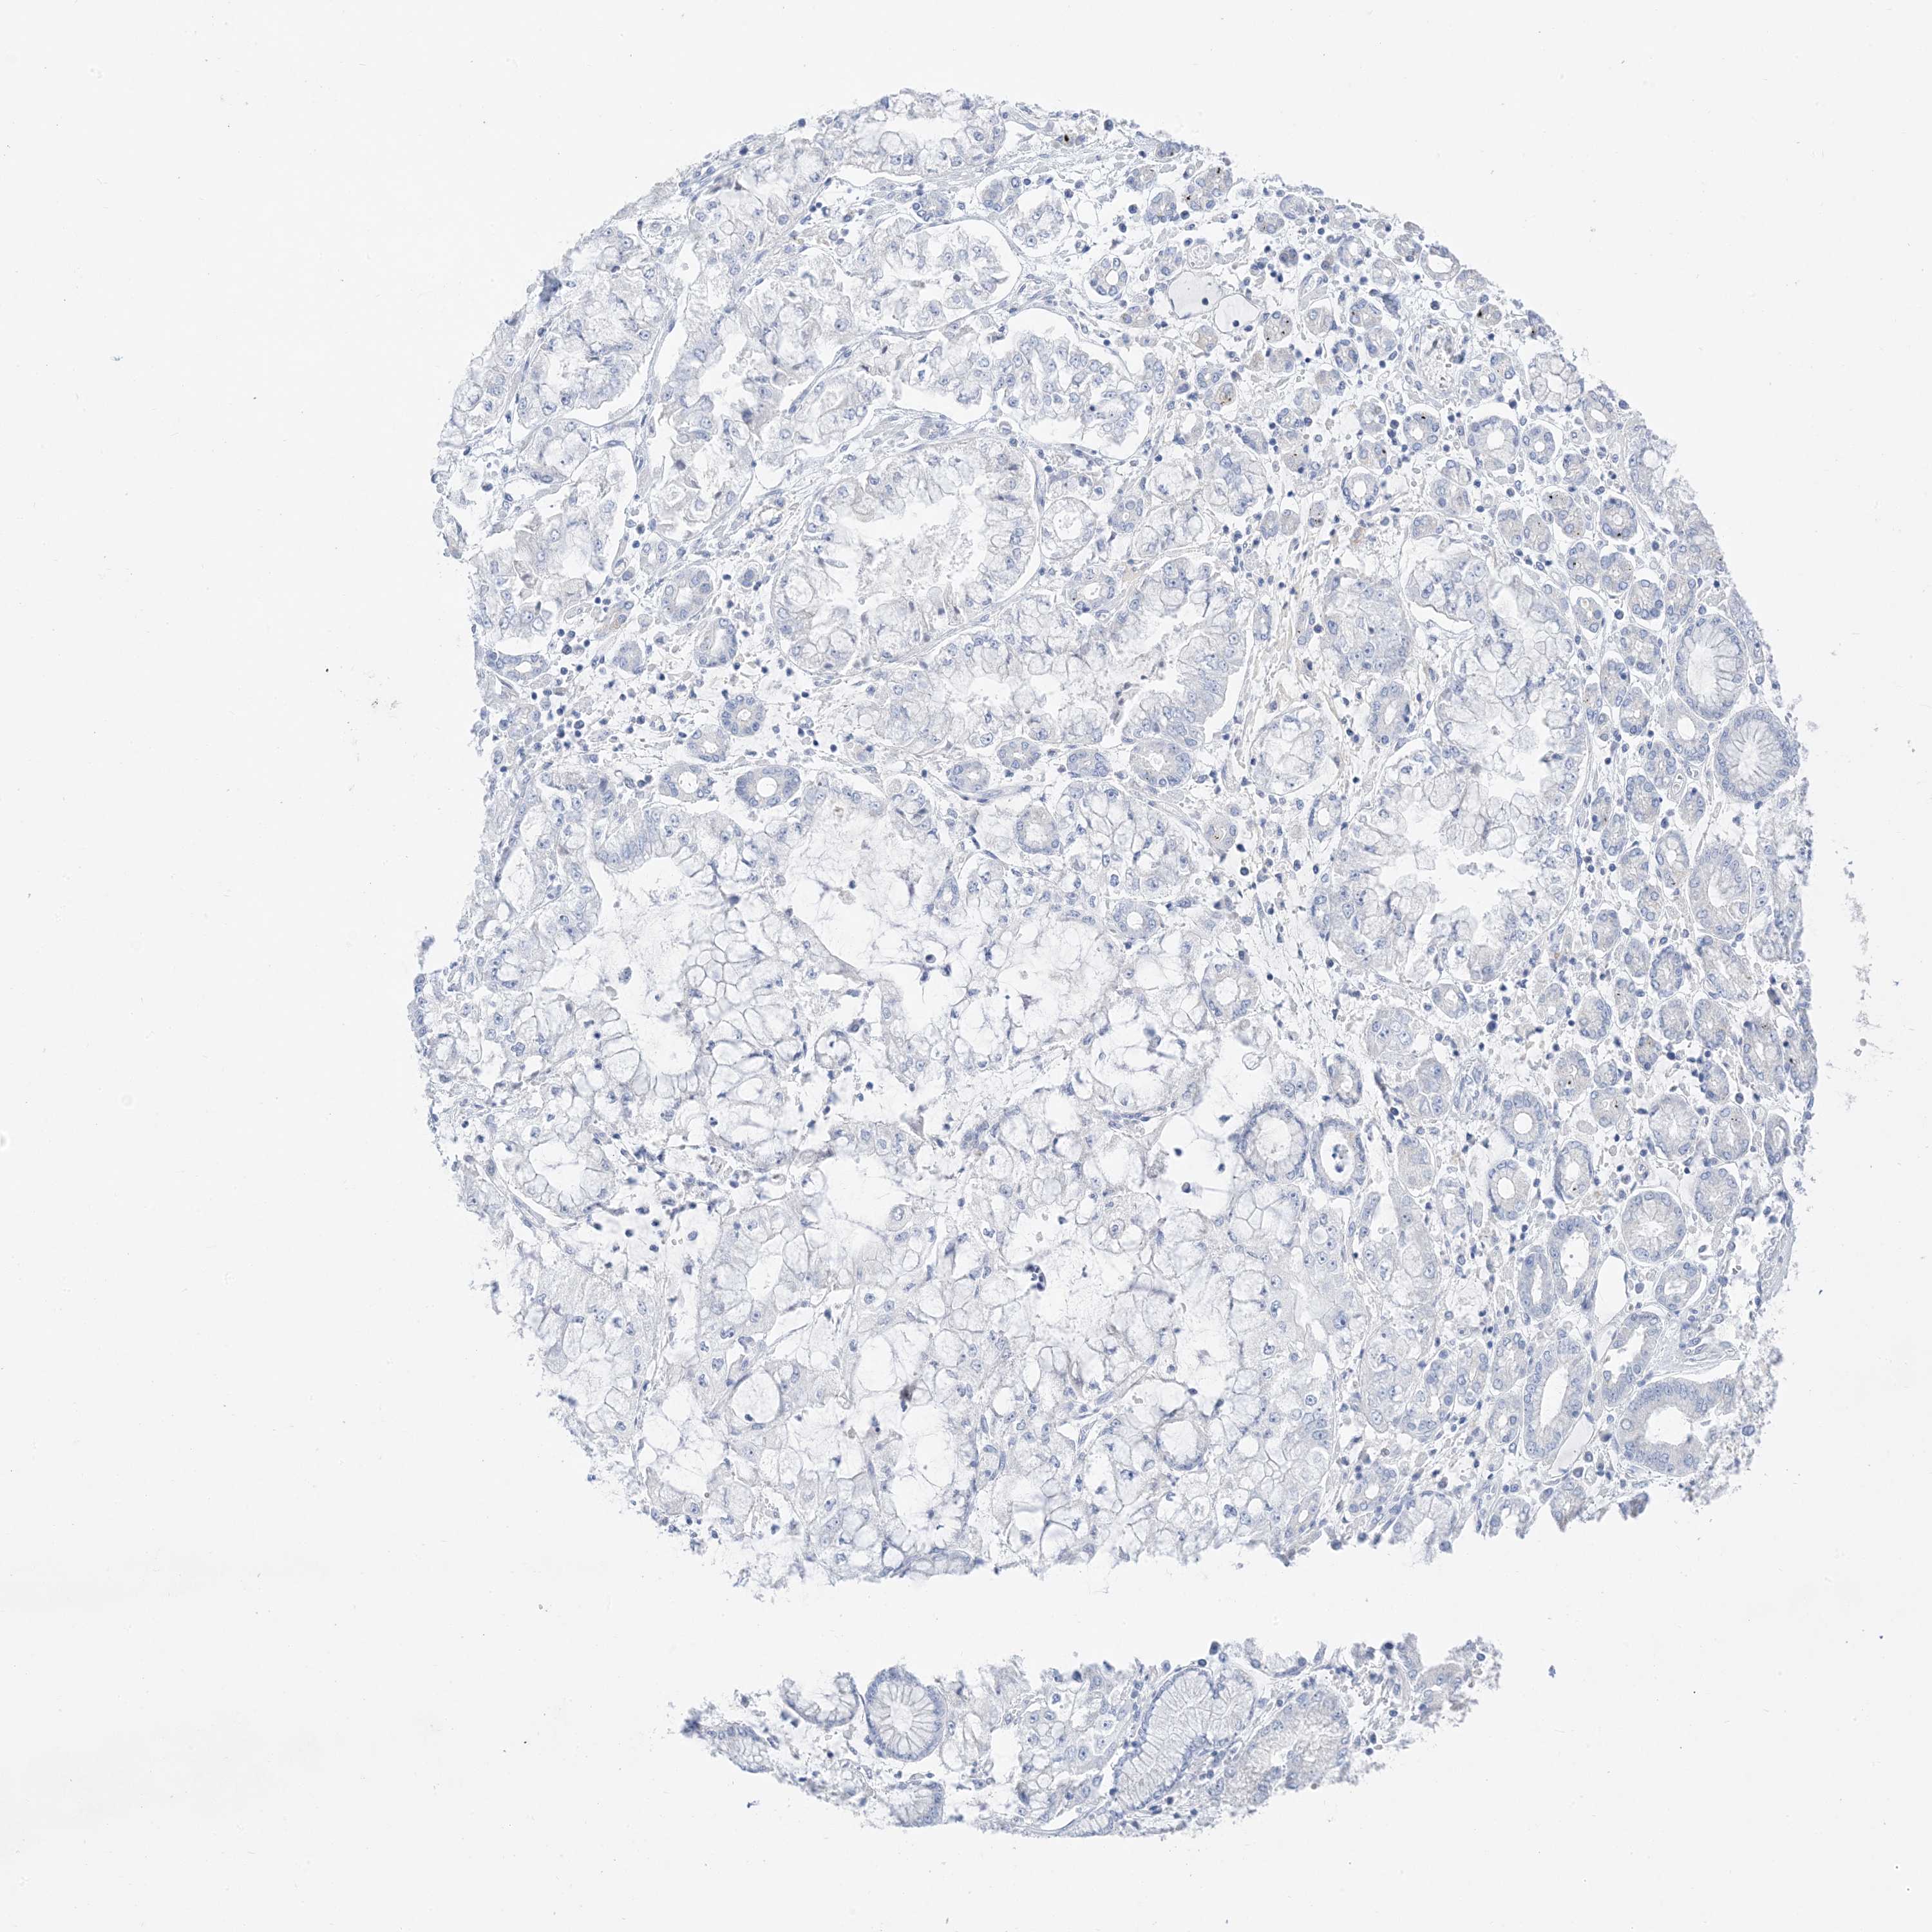

STOMACH CANCER - Protein expressioni

A mouse-over function shows sample information and annotation data. Click on an image to view it in a full screen mode. Samples can be filtered based on level of antibody staining by selecting one or several of the following categories: high, medium, low and not detected. The assay and annotation is described here.

Note that samples used for immunohistochemistry by the Human Protein Atlas do not correspond to samples in the TCGA dataset.

Antibody stainingi

Antibody staining in the annotated cell types in the current human tissue is reported as not detected, low, medium, or high, based on conventional immunohistochemistry profiling in selected tissues. This score is based on the combination of the staining intensity and fraction of stained cells.

Each image is clickable and will lead to virtual microscopy that enables deeper exploration of all samples and also displays staining intensity scores, fraction scores and subcellular localization as well as patient and tissue information for each sample.

Antibody HPA031634

Antibody CAB080501

Antibody CAB080502

Antibody CAB080503

Adenocarcinoma, NOS

Adenocarcinoma, High grade